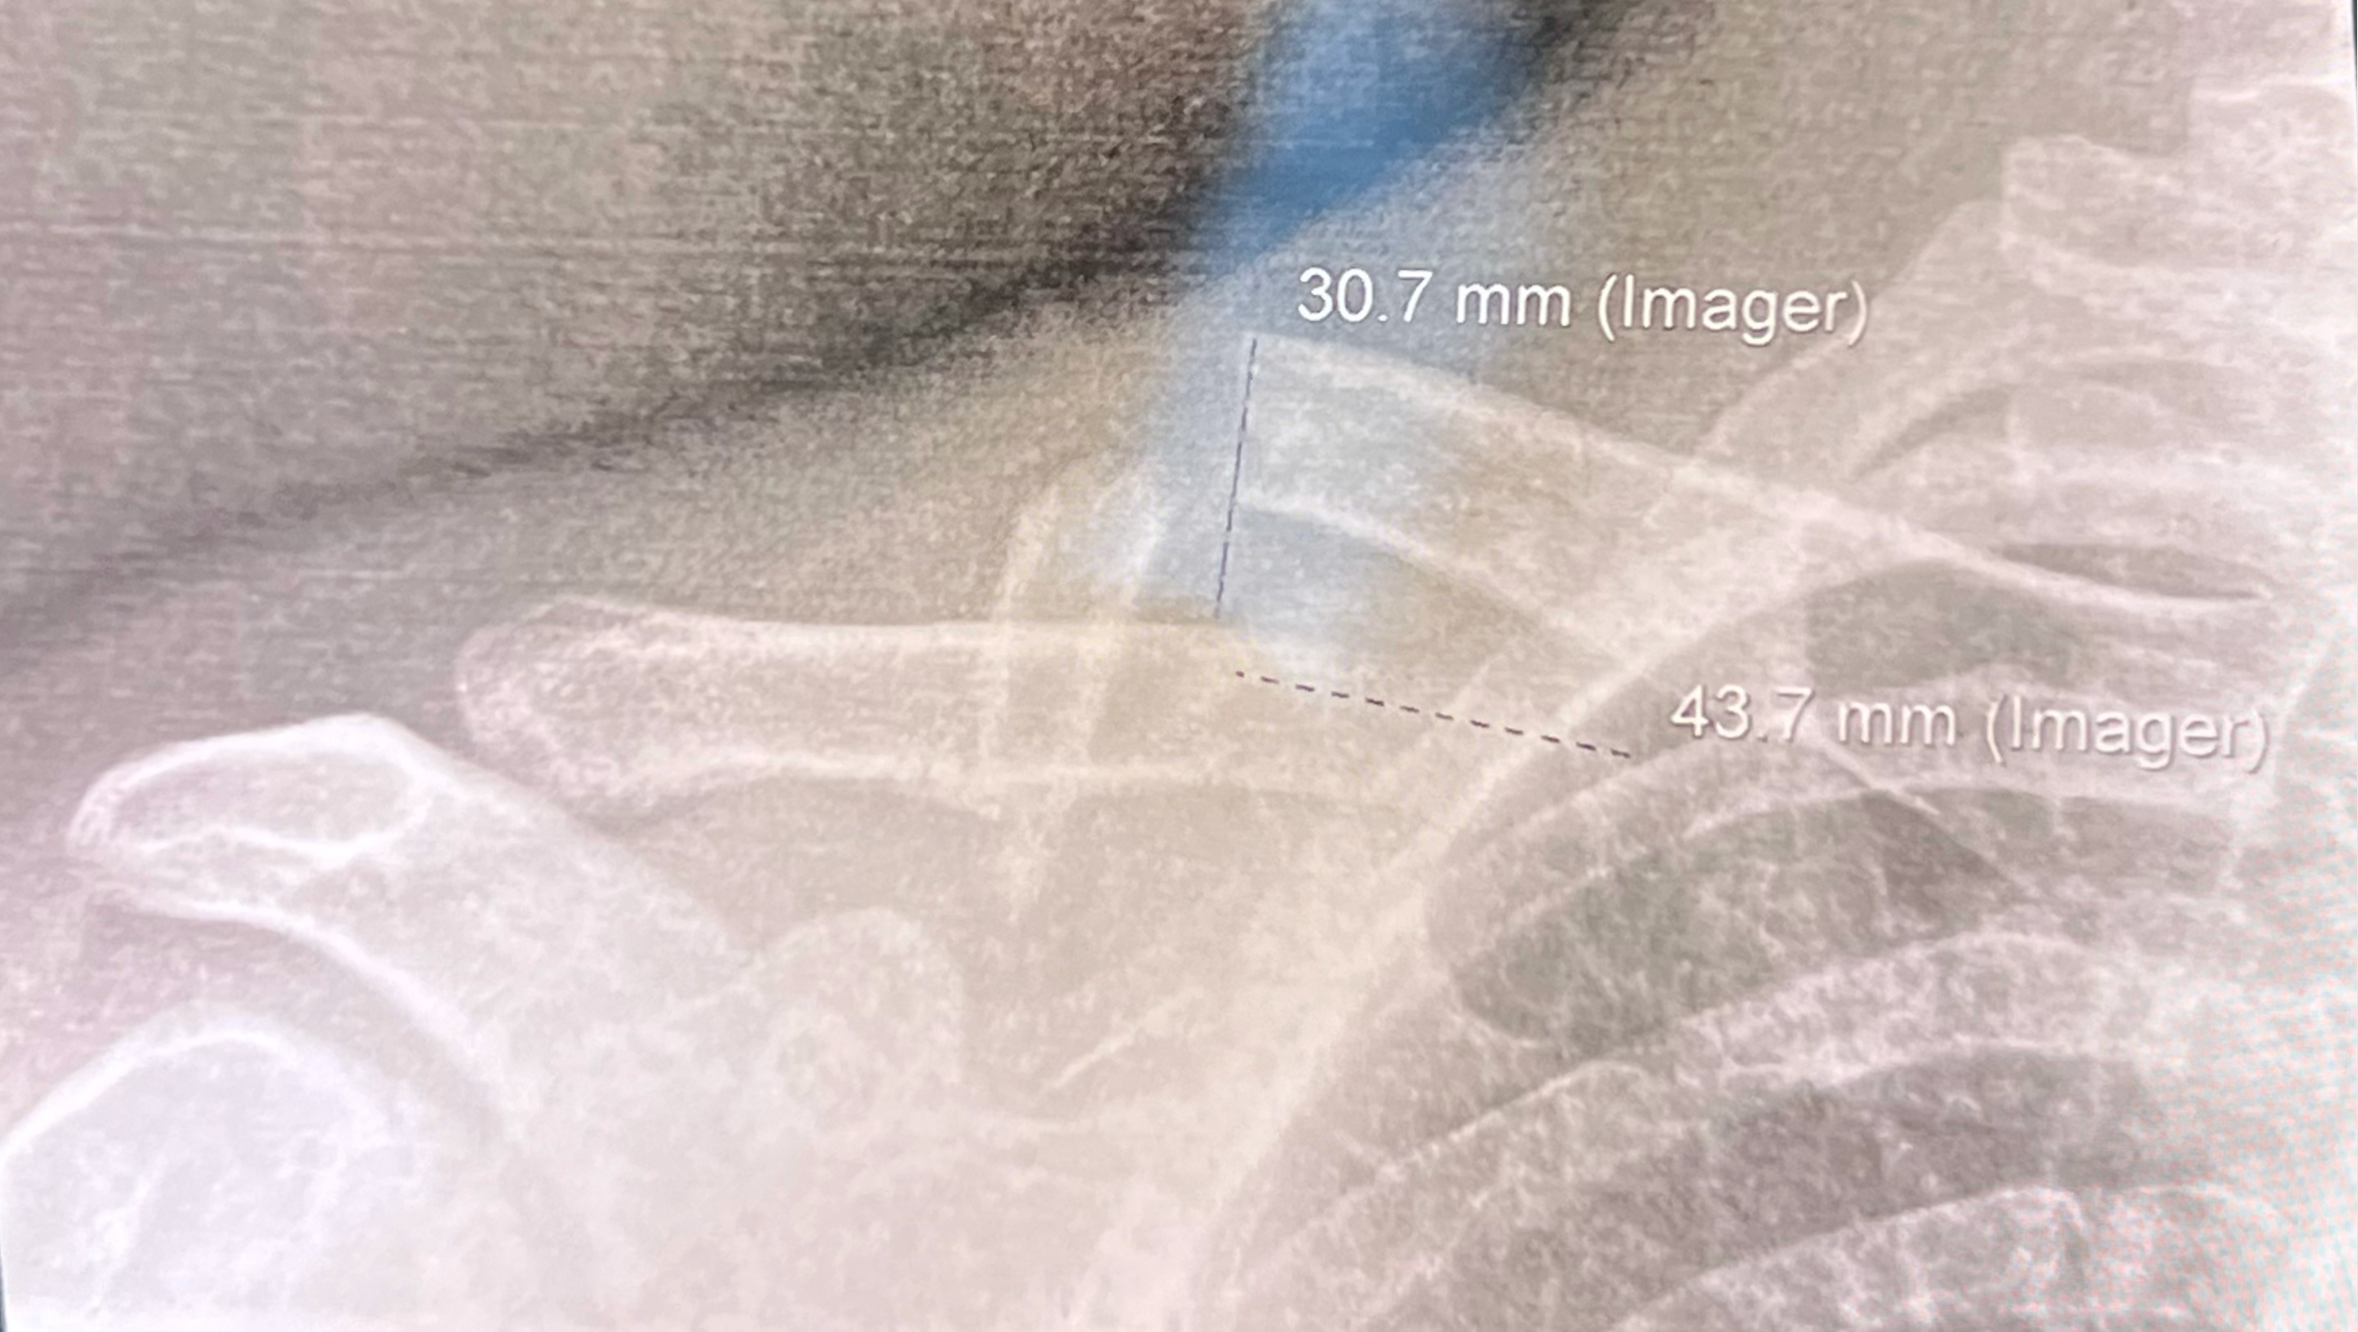

One of our Sushi Chefs, Jordan Howard was involved in a hit-and-run accident in SF on his way to work at Robin. He has suffered a broken collar bone, and unfortunately his medical insurance will not begin until the first of May. We are trying to raise some money to support his recovery and impending medical bills. We hope to have Jordan back at Robin as soon as possible.